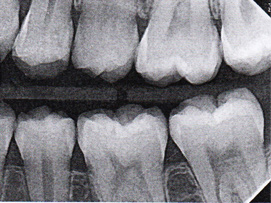

Fig 5. Three thin soft dental picks were used simultaneously for SDF proximal surface saturations in a teenaged patient (Fig 3). After 60 seconds, the treated regions were covered with 5% fluoride varnish (Fig 4). A comparison can be seen of pre-SDF-treatment bitewing films (Fig 5) and 8-month post-SDF bitewing films (Fig 6) for the patient shown in Fig 3 and Fig 4. Radiolucencies were similar or improved, except for contact of maxillary first and second molars.

Figure 5

Fig 6. Three thin soft dental picks were used simultaneously for SDF proximal surface saturations in a teenaged patient (Fig 3). After 60 seconds, the treated regions were covered with 5% fluoride varnish (Fig 4). A comparison can be seen of pre-SDF-treatment bitewing films (Fig 5) and 8-month post-SDF bitewing films (Fig 6) for the patient shown in Fig 3 and Fig 4. Radiolucencies were similar or improved, except for contact of maxillary first and second molars.

Figure 6

Interproximal insertion of SDF is demonstrated in different patients in Figure 3 through Figure 11. Various diameters and brands of soft dental picks may be used depending on the closeness of the proximal surfaces and ease of insertion; for example, some picks are designed for use in wider spaces between teeth. This protocol also offers versatility. Figure 3, for example, shows the simultaneous use of three thin soft dental picks to saturate proximal surfaces with SDF in a teenaged patient; the treated regions were subsequently covered with fluoride varnish (Figure 4). This patient was initially treated in April 2019 (Figure 5), with an identical re-application 3 months later. As shown in Figure 6, the December 2019 bitewing film revealed good results with the possible exception of the contact regions of the maxillary first and second molars. New SDF application was completed in the December appointment.

The senior author's (TPC) private practice experience with soft-tip insertion of SDF into contacting proximal surfaces of teeth is that most beginning proximal surface caries lesions cease to progress, as evidenced by subsequent bitewing radiographic comparisons (Figure 3 through Figure 6, Figure 12 through Figure 18). The chances for success vary, however, depending on frequency of application, subsequent flossing by patients or adults flossing younger children, diet control, individual mouth chemistries, and use of fluorides for the topical effect. It must also be emphasized that office staff should make extensive efforts to inform children and parents that subsequent daily flossing is needed to accompany SDF treatments; otherwise, SDF applications will only delay the inevitable progression of caries. Flossing methods should be demonstrated for patients and for parents so they may see how to floss younger children. Showing them enlarged graphic photographs of flossing results may be helpful in this regard. Parents and patients should be made aware that if interproximal dental plaque accumulations persist without daily interruption by flossing, the acid insult will eventually take its toll on the proximal surfaces and caries lesions will progress to the point where restorative intervention may be required.